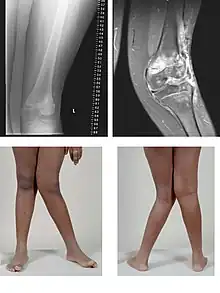

Le genu valgum (dit également « genou cagneux » ou « genou en X ») est une déviation vers l'extérieur de l'axe du membre inférieur avec saillie du genou en dedans : les deux genoux se touchent alors que les chevilles sont écartées.

Est considéré comme anormal un genu valgum asymétrique ou unilatéral, un genu valgum continuant de s'aggraver après l'âge de 4 ans, ou avec une distance intermalléolaire de plus de 8 cm chez le préadolescent. Ce n'est que dans ces cas qu'un bilan radiologique et un avis chirurgical sont indiqués[1].

Le genu valgum est indolore. Dans les formes légères, il régresse souvent avec la gymnastique et la croissance. Dans les formes importantes, le traitement nécessite la prise de vitamine D (contre le rachitisme), le port de chaussures correctrices et la pose d'attelles pendant la nuit. La chirurgie est réservée aux formes graves ; le chirurgien fait une ostéotomie (section osseuse) qui réaligne l'os concerné, puis le fixe.

Chez l'adulte, le genu valgum peut être dû à un genu valgum infantile non traité, à une séquelle de fracture du genou consolidée en mauvaise position ou à une maladie osseuse (ostéomalacie). Il est parfois à l'origine d'une arthrose du genou invalidante. Outre la vitamine D (contre une ostéomalacie), le traitement des formes graves de genu valgum est l'ostéotomie ou, si la situation a évolué depuis trop longtemps, le remplacement de l'articulation du genou par une prothèse.